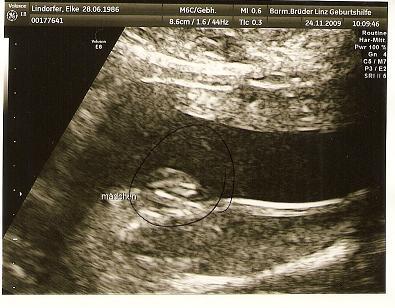

ja sicher bekommt ihr die ;) ja mal sehen ich hab das gesicht meines zwergis das letze mal in der 11 ssw gesehen .. und das ist lange lange her +g+ .. da hab ich auch vorerst das letze foto bekommen habe dawischn und noch ein beweißfoto bekommen ... oh jetzt komm ich drauf hab ich noch garnicht angehängt .. mach ich gleich mal +g+ Fotoerklährung oben der popsch dann rechts weg der Oberschenkel und ja oben ihre mumu ;)

Bild zu